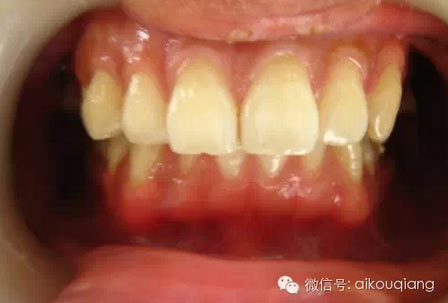

男性成年人喜歡喝茶、抽煙,造成牙齒表面色素沉著,很不美觀

2.jpg

洗牙(潔治)后,潔白如一